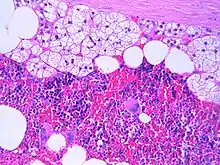

The typical microscopic features of myelolipomas are shown in the image. There is a mixture of normal adrenal tissue, fat, and a full trilineage maturation of the three major blood-forming elements: myeloid (white blood cell forming), erythroid (red blood cell forming), and megakaryocytic (platelet forming) lines.[1]